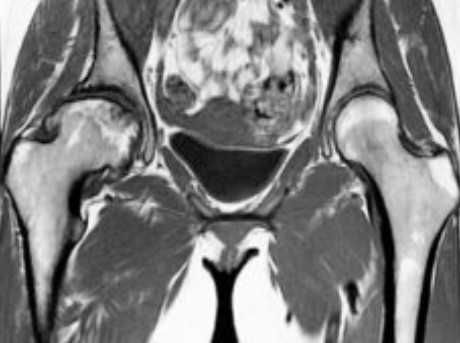

МР-скан коксофеморальных сочленений, вариант нормы

Интерпретацией изображений занимается врач-рентгенолог. В норме на серии томограмм травматических изменений не определяется:

структура костной ткани однородна, без дистрофических признаков;

субхондрального склероза суставных поверхностей нет;

капсула сочленений не утолщена, в полости присутствует небольшое количество синовиальной жидкости с однородным МР-сигналом;

костные крыши вертлужных впадин сформированы правильно, суставные щели равномерные, конгруэнтность (сопоставимость, согласованность) поверхностей сохранена;

целостность связочного аппарата не нарушена;

сигнал хрящевого компонента без особенностей, областей истончения нет;

краевые заострения суставных поверхностей вертлужных впадин отсутствуют;

окружающие мягкие ткани без видимой патологии;

бедренные и тазовые кости в зоне сканирования без очаговых изменений.